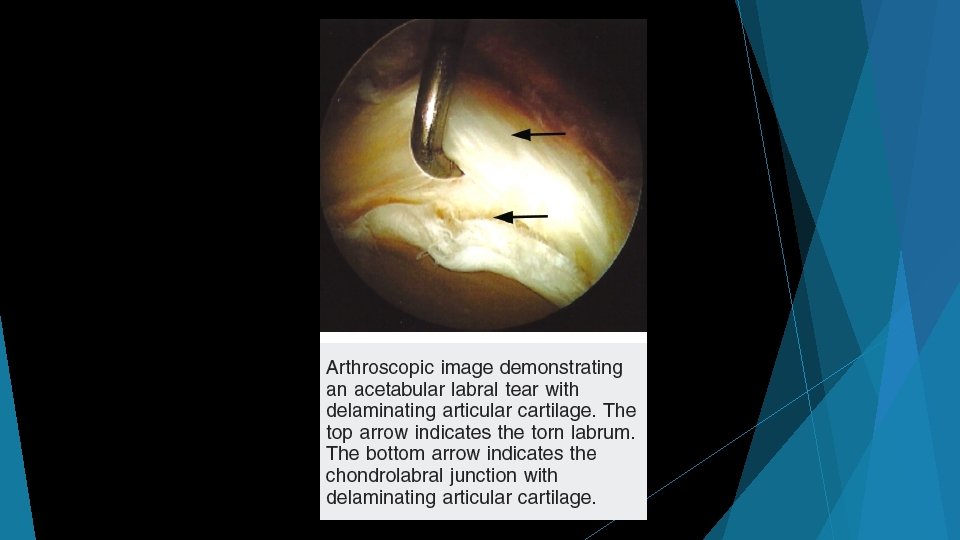

Shear forces on cartilage at chondrolabral junction Impingement with hip flexion Subtle findings on MRI: marcaine arthrogram with traction, 1. 5+ T MRI